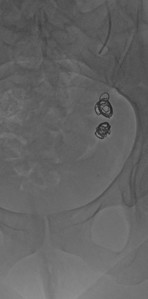

Nach Kathetereinführung über eine Armvene rechts in örtlicher Betäubung Röntgen-Kontrastdarstellung der krankhaft erweiterten Ovarialvene links mit abhängigen Krampfadern um die Gebärmutter und innere Beckenvenen. Verschluss derselben mittels Metallspiralen (Coils) und einem Verödungsmittel.